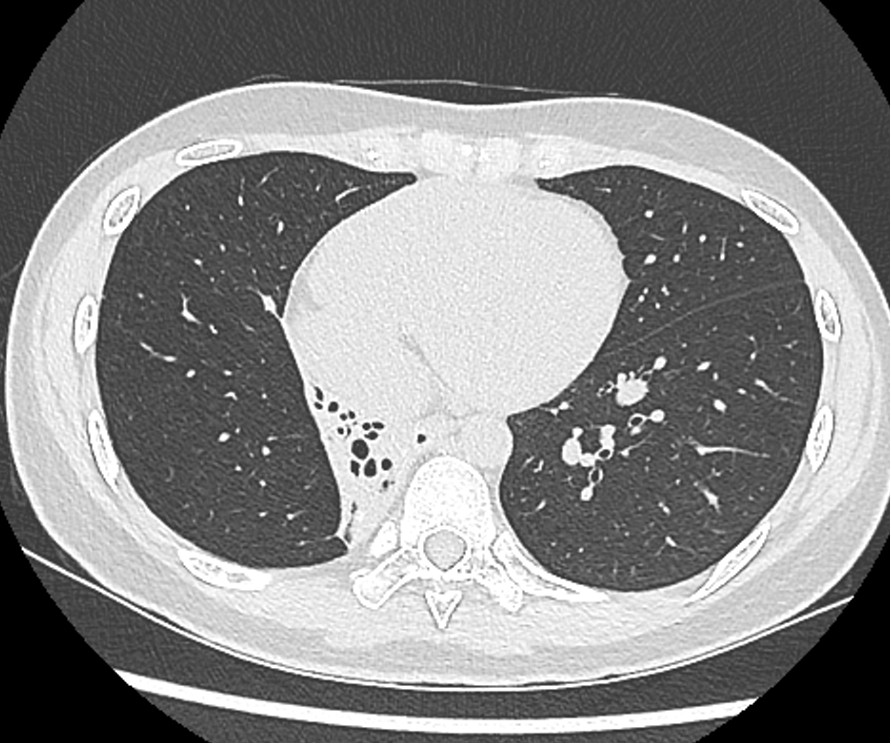

患者2年前无明显诱因出现咳嗽,偶有少量黄色痰液,无发热,无盗汗,无咯血,无胸闷、胸痛,就诊于我院肺科,痰结核菌涂片提示阳性,胸部CT提示右肺下叶感染性改变,考虑继发性肺结核伴支气管扩张,予抗结核治疗1年后遵医嘱停药。患者仍间断咳嗽,咳脓痰,反复发作,间断加重,严重影响生活,为进一步治疗,就诊于我院胸外科门诊,复查胸部CT提示右肺中叶及下叶萎陷不张,不张肺组织内支气管扩张及散在钙化灶。以“,继发性肺结核,右侧毁损肺”收入院。下图是患者胸部CT,显示右肺中下叶肺毁损。